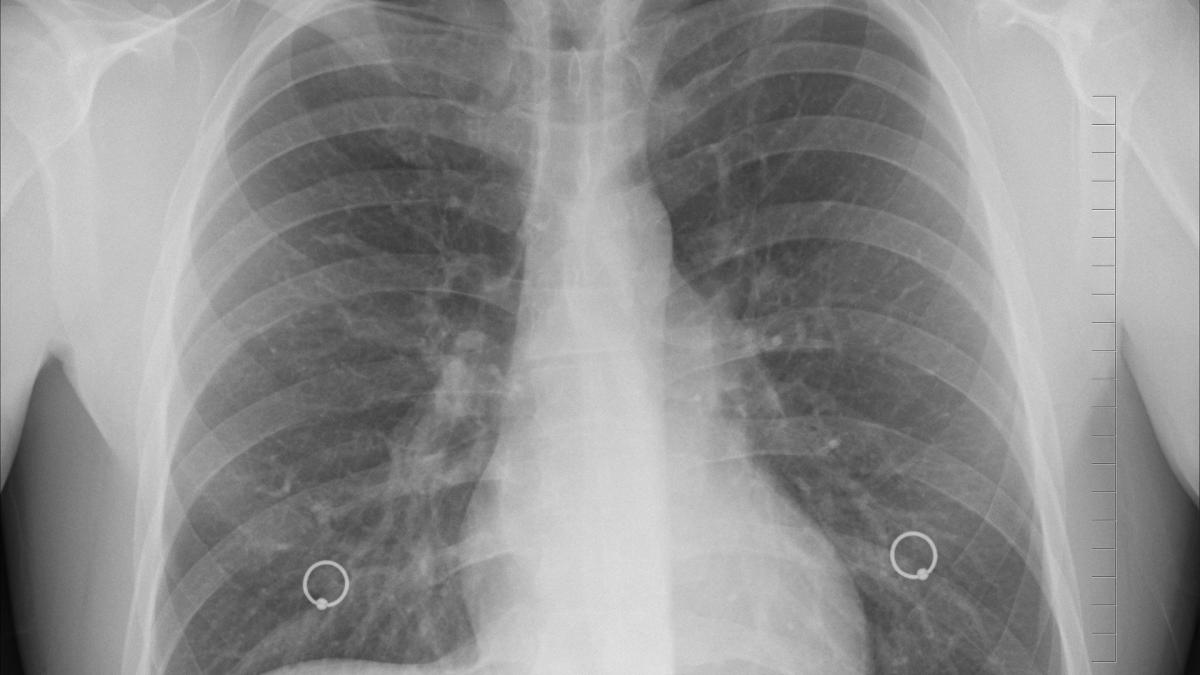

Imagini cu plămâni afectaţi de COVID în proporţie de 80%. Medic: "Fără oxigen, aceşti oameni ar fi murit, cu siguranţă"08 Iun

Managerul spitalului Marius Nasta ne arată cum sunt plămânii unui pacient cu COVID, în formă moderată şi critică!26 Aug

Cum arată plămânii unui infectat cu COVID-19. Managerul Institutului ”Marius Nasta”: ”Apare un sindrom complex, care nu poate fi ținut sub control de către medici”16 Mar